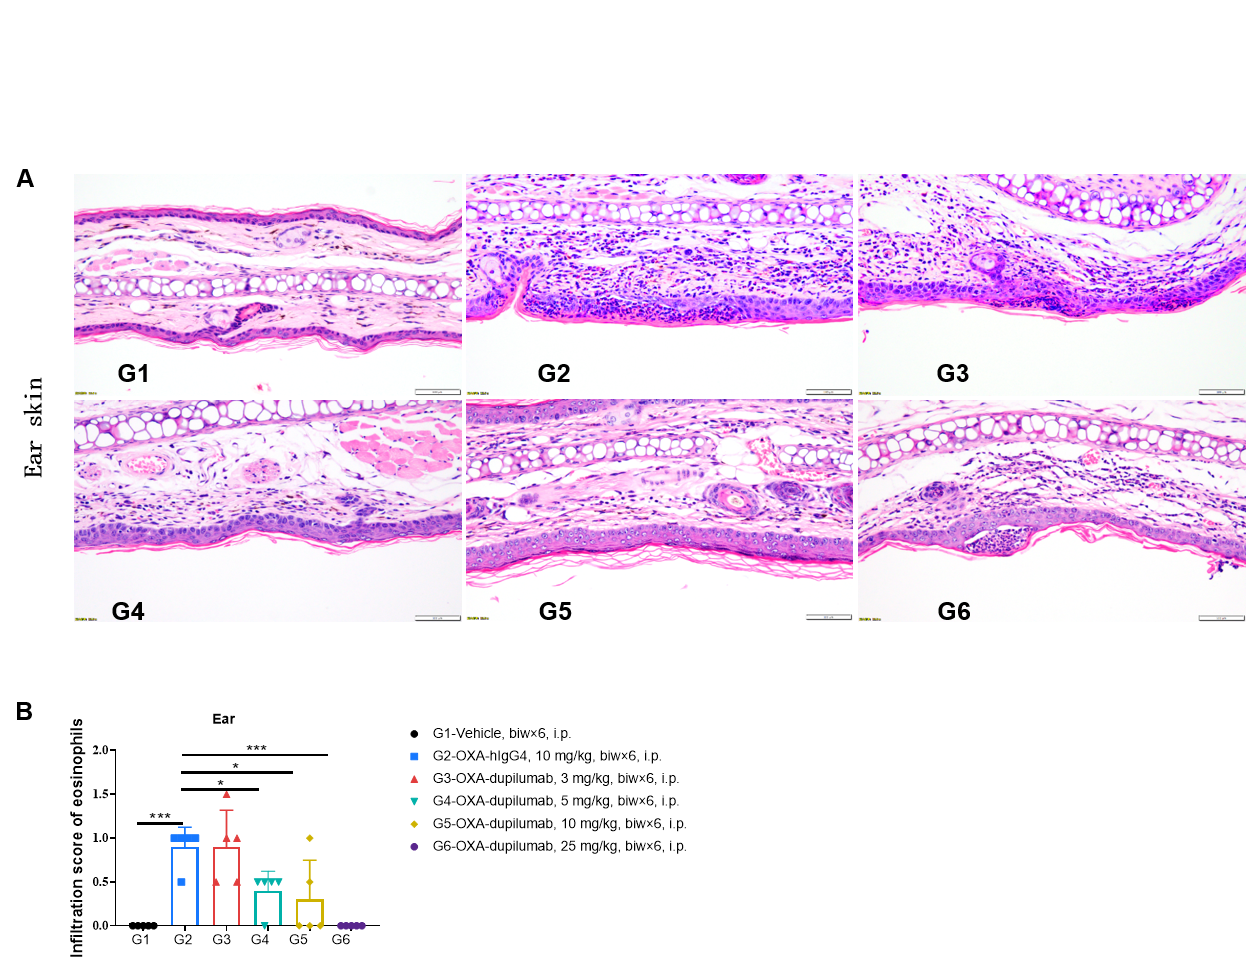

Effects of anti-human IL4RA antibody on inflammatory infiltration in ear skin of the AD mouse model. (A) Hematoxylin and eosin (H&E) staining. (B) Score of eosinophils infiltrated in ear epidermal skin (n=5). Infiltration scores of eosinophils in ear skin were negatively related to the doses of antibody, demonstrating that the B-hIL4/hIL4RA mice provide a powerful preclinical model for in vivo evaluation of anti-human IL4RA antibodies. AD: Atopic dermatitis; ND: Not detectable.